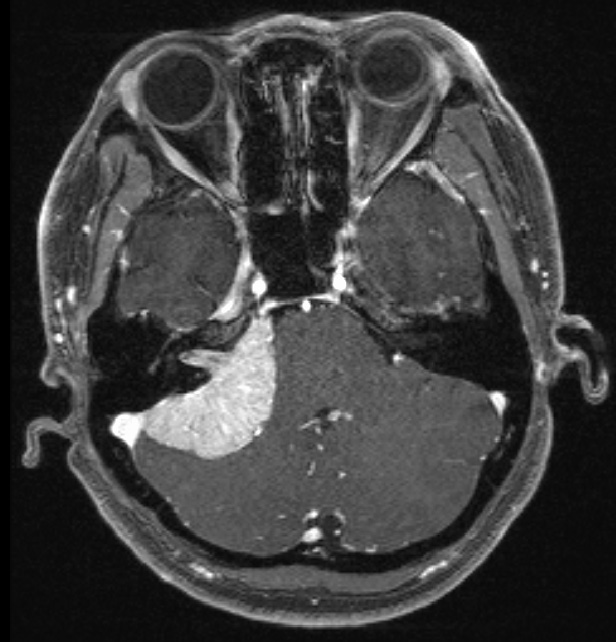

外視鏡と内視鏡を組み合わせて治療した腫瘍のMRI画像です。

髄膜腫:小脳、脳幹、聴神経などが圧迫されている

術前MRI